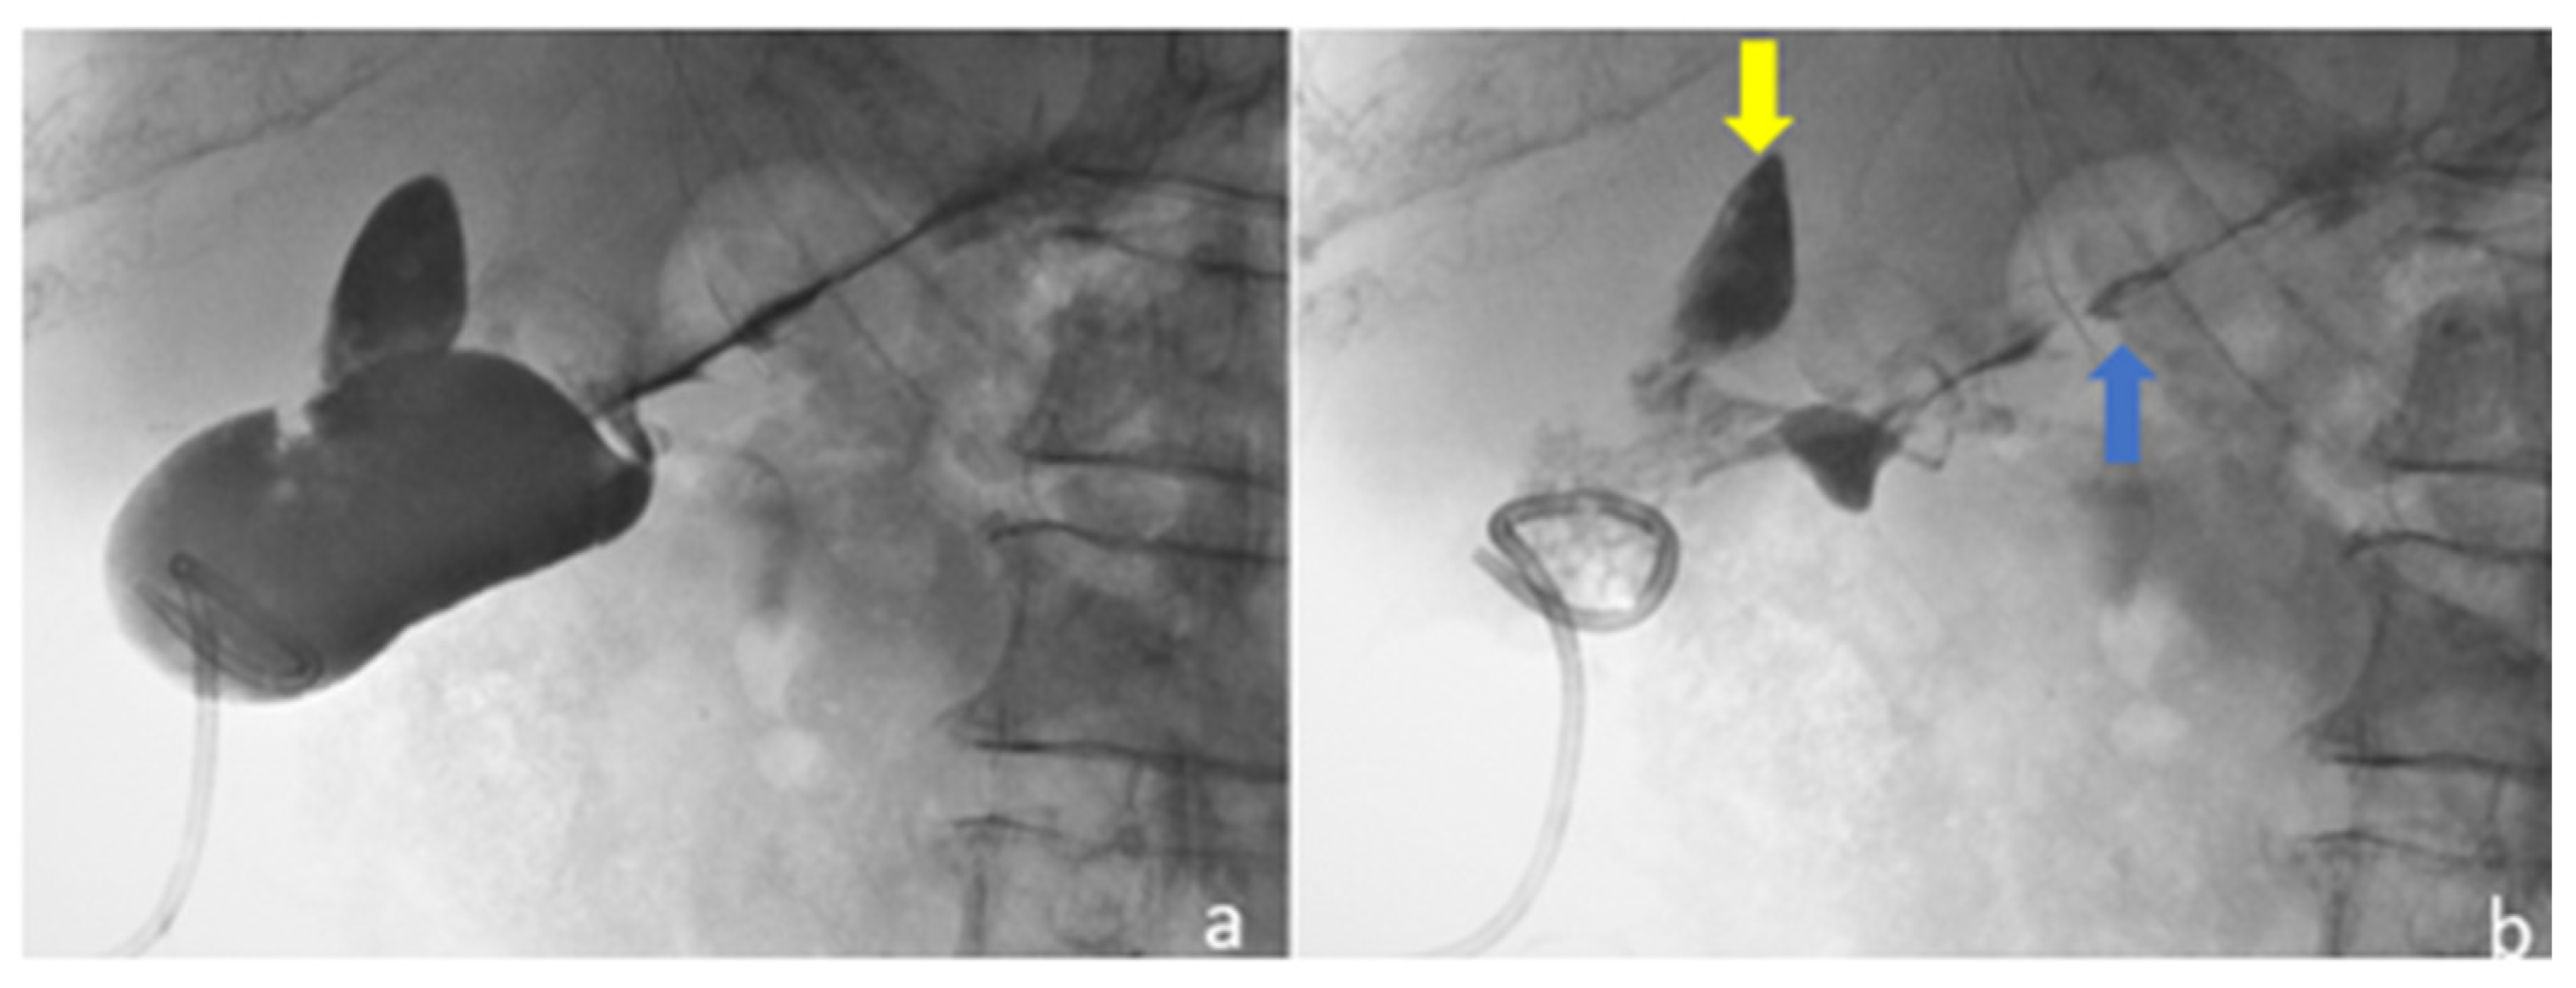

2.1. Case 1

2.2. Case 2

2.3. Case 3